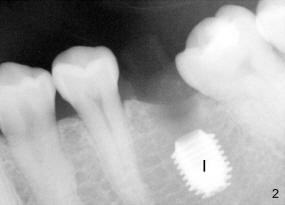

The tooth #19 has been lost for 8 years with tilting of #18 (black line in Fig.1). A 6x8 mm Bicon implant (3 mm post) was placed as distal as possible (I in Fig.2). Three months later, the implant was uncovered with evidence of osteointegration (arrowheads in Fig.3). A 4x6.5 mm 0 degree non-shouldered abutment with 3 mm post (A) was inserted into the implant well. The flat surface of the abutment needed to face distal in order to seat the abutment without interference. The implant/abutment complex was used as an anchorage to upright #18. The tooth #17 was extracted prior to orthodontic treatment (compare Fig.5,6 vs. 1-3). A bracket was bonded to Jet temporary crown of #19 and open coil spring was placed between #18 and 19. In the first two months, distalization of #18 is limited (between black and white lines in Fig.4), partially due to the fact that the bracket of #19 was debonded quite easily. A premolar band (B in Fig.5) was cemented to the temporary crown of #19. In another two months, the tooth #18 was pushed to desired position (arrowhead) under the tension of open coil spring (*). The mesial crest height of #18 was increased during uprighting (arrow, as compared to Fig.1-3). A new temporary crown was fabricated to fit the enlarged space of #19 with cementation of a molar band. The next problem is that the new molar temporary crown was easily dislodged from the 4x6.5 mm abutment even with a permanent cement. A larger abutment (5x6.5 mm) was used (Fig.6), with relining the temporary crown. The upper end of the larger abutment has sharp edge (Fig.8: white arrowhead, as compared to rounded edge of the smaller abutment (Fig.7). This may also contribute to better retention. In another 3 months, the temporary crown was dislodged again. An even larger abutment (6.5x6.5 mm with two flat surfaces (blue arrowheads in Fig.9) was adopted.